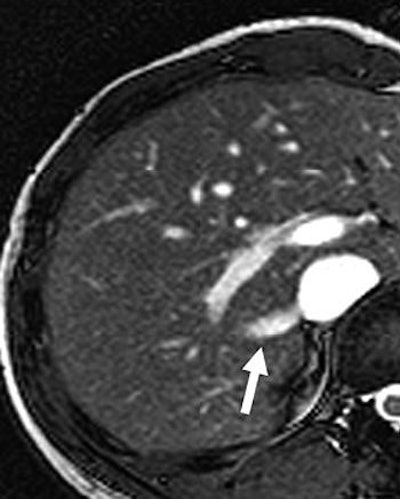

| Twenty-year-old man with large right inferior accessory hepatic vein. Balanced turbo field-echo images (above, axial image; below, coronal image) reveal a 7.3-mm right inferior accessory hepatic vein (arrow) entering inferior vena cava. Lim JS, Kim M, Kim JH, Kim SI, Choi J, Park M, Oh YT, Yoo HS, Lee JT, Kim KW, "Preoperative MRI of Potential Living-Donor-Related Liver Transplantation Using a Single Dose of Gadobenate Dimeglumine" (AJR 2005;185:424-431). |